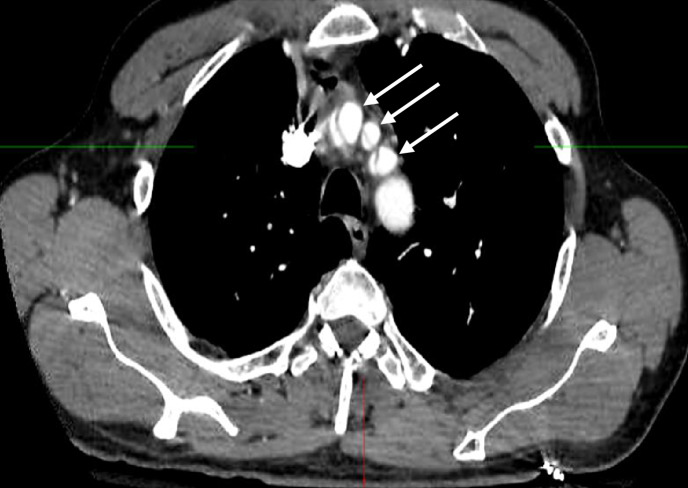

Case presentation: We report a patient with a chronic Stanford type A aortic dissection with dissection extension into the left common carotid artery and left internal carotid artery who had a good clinical outcome following mechanical thrombectomy for a symptomatic middle cerebral artery occlusion. We also review other cases in which endovascular mechanical thrombectomy was conducted in patients with aortic dissection and acute ischemic stroke and discuss the potential risks and benefits of carotid artery stenting in this clinical situation.